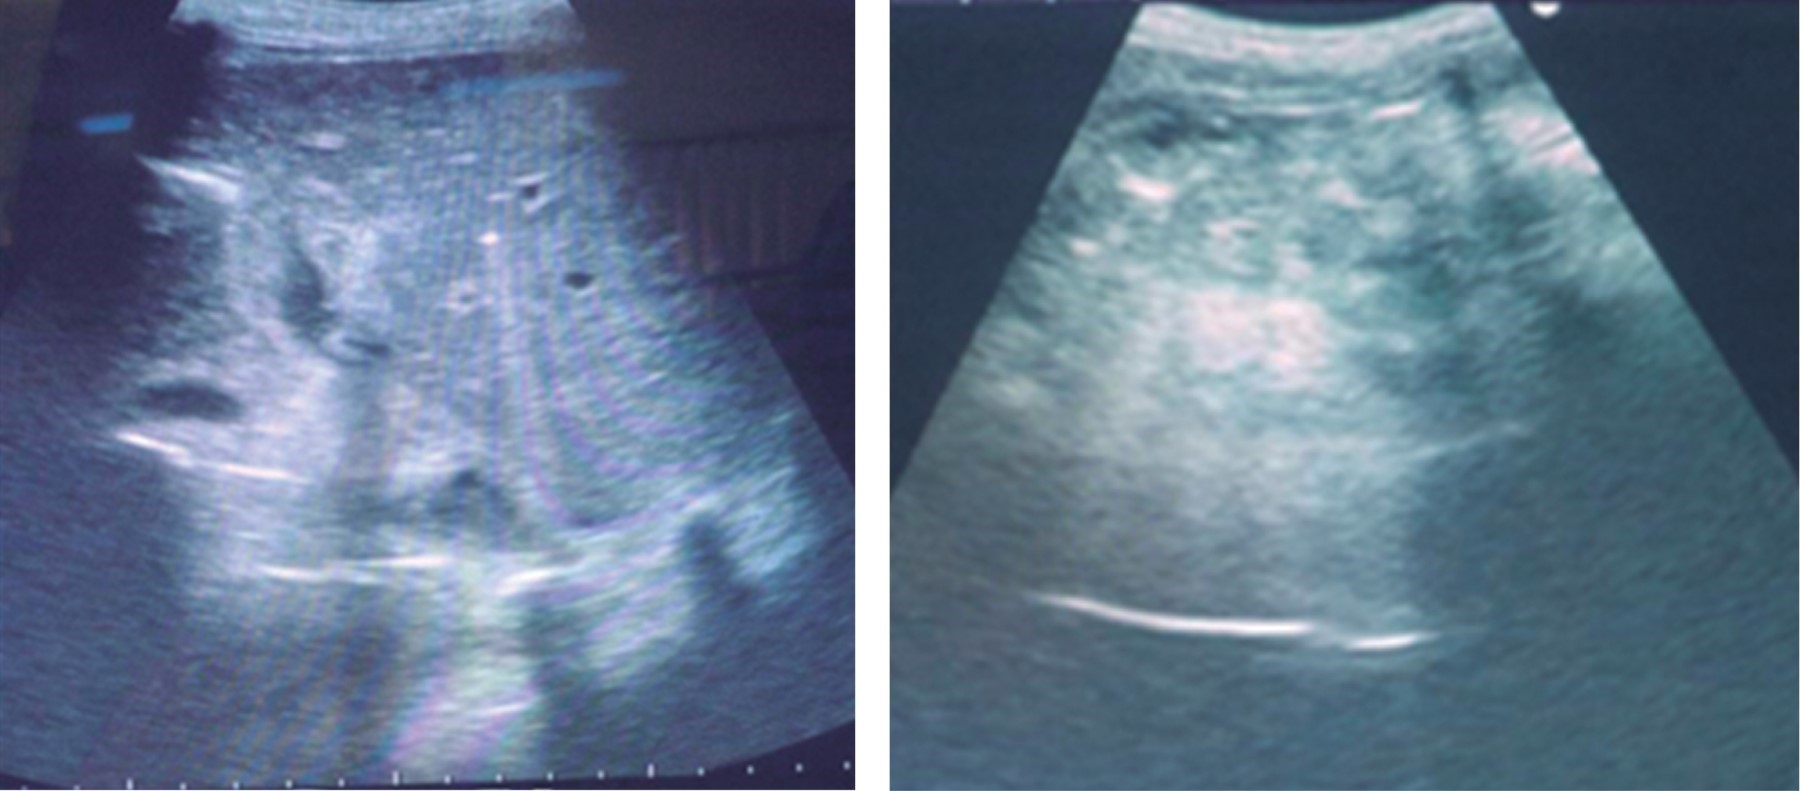

Es evaluada en conjunto con el servicio de nefrología, nutrición y neurocirugía, recibe durante su hospitalización tres unidades de concentrado globular, control de balance hídrico, control paraclínico, hemodinámico, de gasto por drenes y manejo de sonda pleural, más curación diaria de herida. Al quinto día de hospitalización se retira dren dirigido a fondo de saco, por ausencia de gasto. En su noveno día, en vista de salida espontánea de dren dirigido a Morrison manteniendo aún gasto biliar, se le realiza recanulación del mismo ecoguiada (Figura 3). Al décimo día se efectúa retiro de tubo de drenaje torácico por evidenciarse expansibilidad pulmonar. Con posterior egreso.

Figura 3